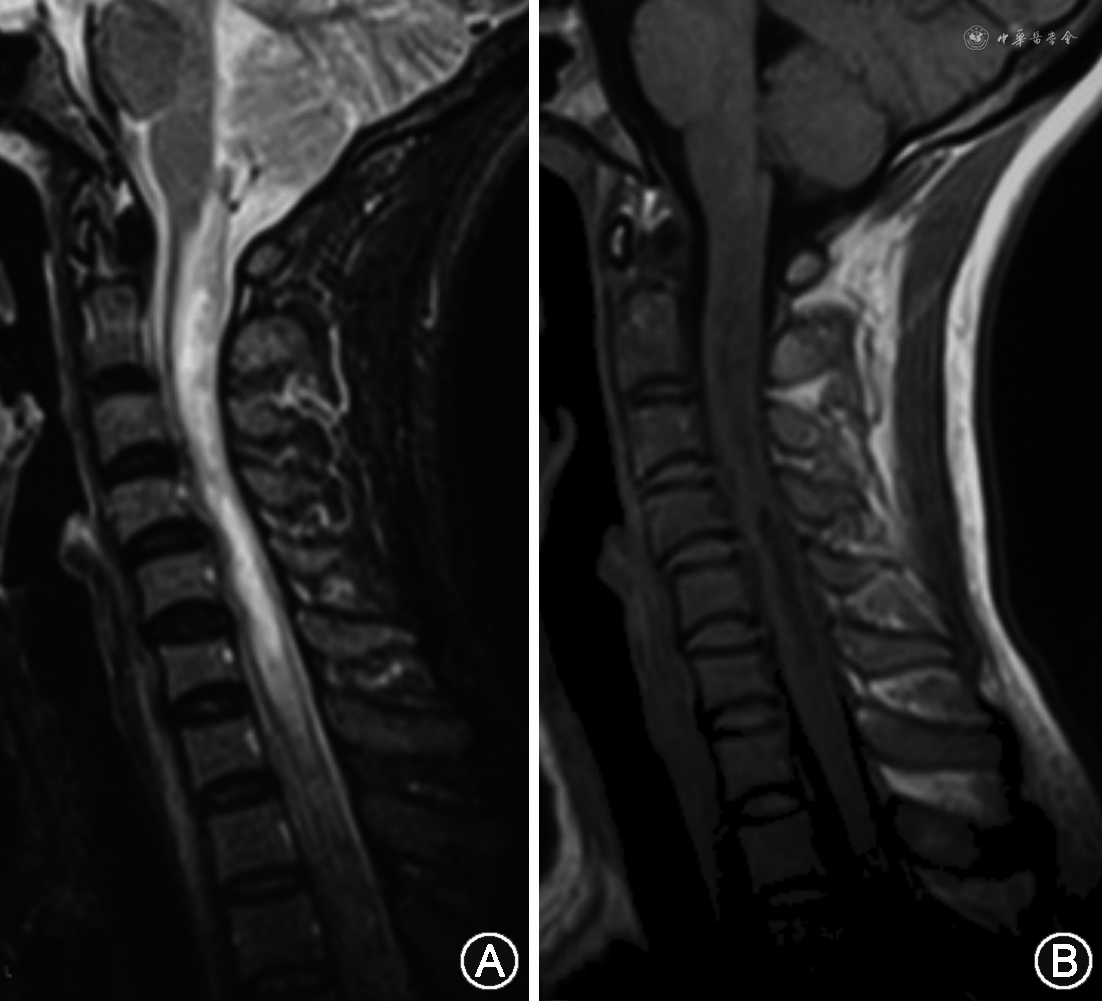

2.急性脊髓炎:MRI显示特征性脊髓纵向延伸的长节段横贯性损害,矢状位可见连续病变,超过3个或以上的椎体节段,少数病例几乎纵贯全脊髓,颈髓病变可向上与延髓最后区病变相连。轴位病变多累及中央灰质和部分白质,呈圆形或H型,后索易受累。急性期病变可见明显肿胀,呈长T1、长T2表现,增强后部分呈亮斑样或斑片样、线样强化,相应脊膜也可强化。慢性恢复期可见脊髓萎缩或空洞(仍需符合超过3个或以上的椎体节段;图2,3A~C)。长节段病变可转变为间断的不连续长T2信号。少数脊髓病变首次发作可<2个椎体节段。